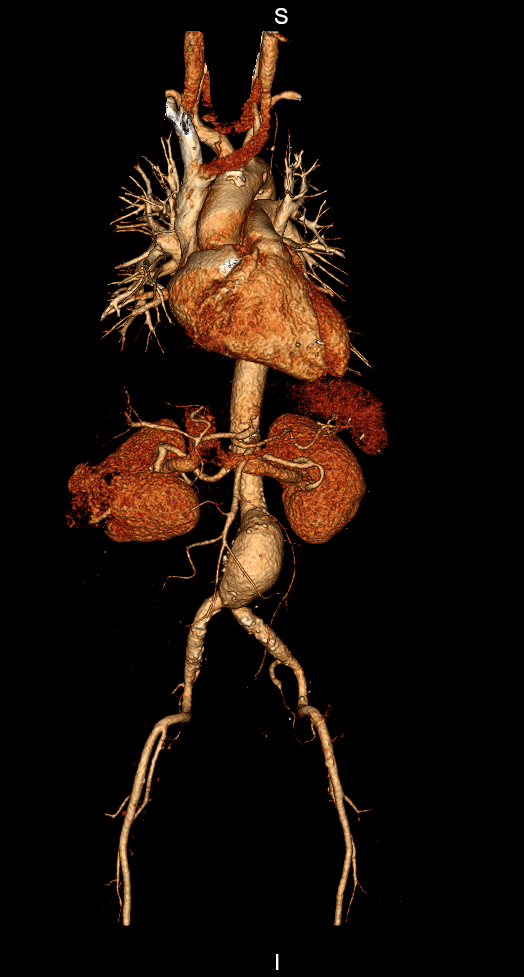

A angiotomografia é indicada quando existe a necessidade de examinar veias e artérias de determinadas regiões do corpo. Isso pode ocorrer devido à suspeita de aneurismas, estenoses, oclusões ou para acompanhamento preventivo de complicações vasculares após cirurgias.

Angio TC (torácica ou abdominal) – Algumas Indicações: síndrome aórtico agudo (rotura de aneurisma ou disseção da aorta).

A maior indicação para a angiotomografia de membro superior e inferior é a avaliação de obstruções arteriais (por tromboses ou estreitamentos), embora algumas tromboses venosas também possam ser diagnosticadas. Podem ser realizadas reconstruções multiplanares e em 3D.